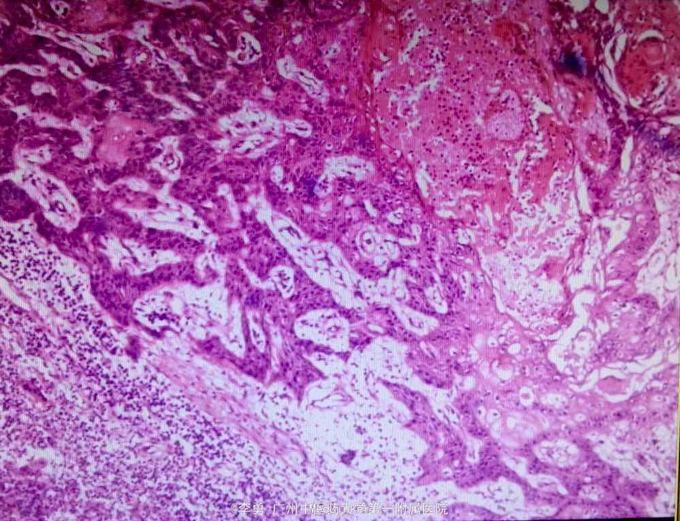

查体:右下肢膝关节外侧皮肤肿物,15*6*3大小,质软,呈菜花状,表面黄白色分泌物,肤温正常,患侧肢体远端血运正常。 辅查:肿物病理活检提示鳞状细胞癌。

诊断:鳞状细胞癌 处理:外科手术切除肿物。